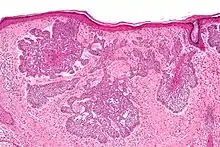

صورة مجهريّة لسرطان الخلايا القاعديّة تظهر الصّفات النّسيجيّة المميّزة (التّطويق المحيطي، سَدى مخاطيّة و (artefactual clefting باستخدام صبغة .H&E تتمايز الخلايا المصابة بسرطان الخلايا القاعديّة إلى خلايا جُرَيْبيّة، مُفْترَزة ودُهنيّة وتكوّن ما يسمّى بال trichoblast, وبالتّالي يصعب التّمييز بين هذا المرض وما يسمّى بالtrichoblastic carcinoma ؛ و هو مرض نادر وخبيث.[8] عدّ بعض العلماء سرطان الخلايا القاعديّة من أنواع ال trichoblastic carcinoma، ولكن لم يُتّفق على هذا التّصنيف إلى الآن.[9] ويُسبّب التّعرض المفرط لأشعّة الشّمس ما يسمّى بمَثْنَوي الثّايمين؛ شكل من أشكال تلف الحمض النّووي ينتج عن تكوّن روابط من نوع ثايمين-ثايمين. ويقوم الجسم عادةً بإصلاح ما يتلف من الحمض النّووي نتيجة التّعرض للأشعّة فوق البنفسجيّة، لكن لا تقوم طرق الإصلاح المختلفة بإزالة جميع الرّوابط التي تكونّت وسبّبت التّلف (مَثْنوي الثّايمين). يؤدّي تراكم التّلف إلى حدوث الطّفرة. وبصرف النّظر عن الطّفرات، التّعرض المفرط لأشعّة الشّمس يثبّط جهاز المناعة في الجسم ونتيجة لذلك فإنّ ذلك قد يقلّل من الرّقابة المناعيّة على الخلايا السّرطانيّة الجديدة. يمكن أن يتطوّر سرطان الخلايا القاعديّة نتيجة الإصابة بمتلازمة وحمة الخلايا القاعديّة (متلازمة غورلين)، وتمتاز هذه المتلازمة بتكلّس مِنْجل المُخ الذي يقع في منتصف الدماغ، تشوّه الأضلاع، إصابة الفك بأورام حميدة سنية المنشأ تسمّى keratocystic odontogenic tumors وظهور وَهْدات (انخفاضات طفيفة في الجلد) في راحة اليد وباطن القدم. وجود طفرة في جين PTCH1 وهو جين كابت يقع على كروموسوم رقم 9 وبالتّحديد على الموقع 9q22.3 و الذي يؤدّي إلى تثبيط ما يسمّى ب hedgehog signaling pathway والذي بدوره يؤدّي إلى الإصابة بالمتلازمة. ويمكن أن يصاب الإنسان بهذا السّرطان أيضاً في حال حدوث طفرة في جين SMO والذي يقوم أيضاً بتثبيط طريق الهيديهوج للإرسال hedgehog signaling pathway.[10]